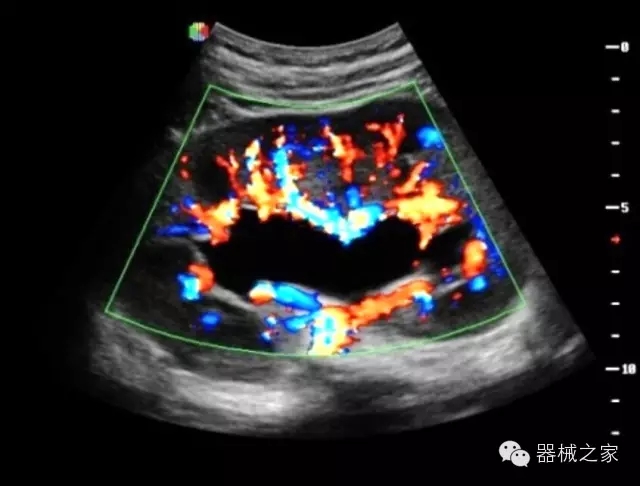

臨床圖片賞析

·獨(dú)有的HoloTM PW 實(shí)時3取樣門PW成像技術(shù),精確進(jìn)行血管診斷;

·一鍵優(yōu)化B、Color、PW,Auto Doppler自動識別血管位置、偏轉(zhuǎn)角度等,提高工作效率;